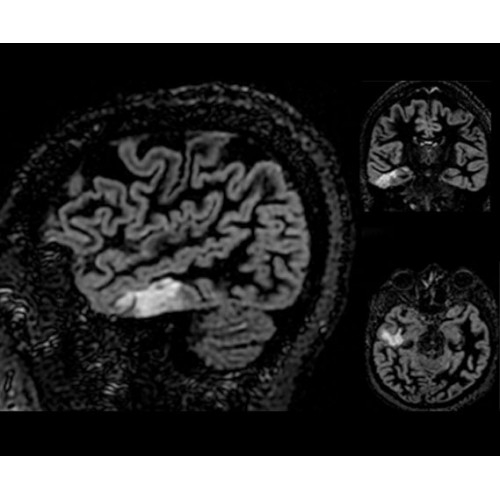

• NeuroWorks — универсальное решение для визуализации анатомии головного мозга, позвоночника, сосудов и периферических нервов с четкой дифференциацией тканей.